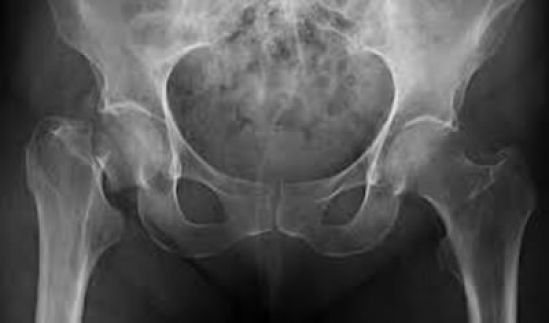

Estadísticas revelan que la prevalencia en México entre mujeres y hombres mayores de 50 años es de 17 y 9% en columna lumbar, respectivamente, y de 16 y 6% en cadera, respectivamente. Se estima que, en nuestro país, el riesgo de fractura de cadera a lo largo de la vida es de 8.5% en mujeres y 3.8% en hombres en el país y que para el 2050 la cantidad anual de fracturas de cadera llegará a 110,055, más de cinco veces la cifra de 20,725 registrada en el 2005 (1,2).